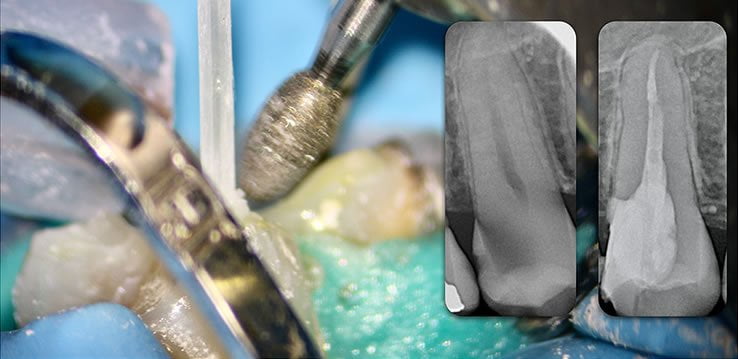

Retain 100% of remaining healthy tooth structure

- Biolight® DRILL-FREE adapts to all shaped canals, while conserving all remaining healthy tooth structure.

- There is no need to drill out portions of canals to accommodate post spaces.

- Easily place multi-posts in multiple canals as the post bends with the natural canal shape.

Biolight® DRILL-FREE posts are available in bundles of 4, 6, 9 and 12 strands. The post size is selected based on the width of the canal at the coronal area. Depending upon the canal width at the apical stop, a certain number of strands must be pushed to the stop. Both of the measurements are made with the assistance of a radiograph and the template that is included in the TRAINING KIT.